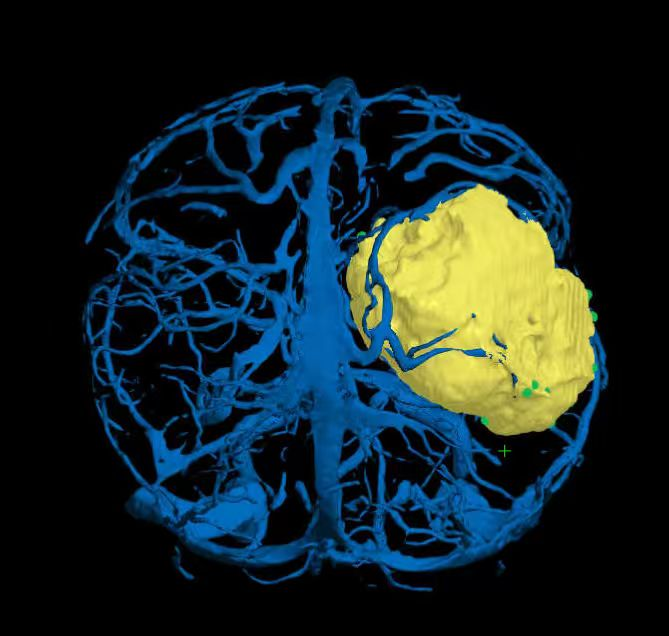

术前精准建模:运用3D Slicer软件整合多模态影像数据重建三维模型,清晰呈现肿瘤与周边功能区、血管的空间关系,为手术规划提供精准数字化依据。

术中实时导航:神经导航系统全程启用,精准匹配术前数据与术中体位,实时定位手术器械位置,成功避开关键功能区及血管,保障操作安全。

CUSA微创切除:采用“瘤内减压+分块切除”策略,借助CUSA超声吸引器精准破碎吸除肿瘤组织,降低对脑组织牵拉,完整保留中央沟静脉及功能区皮层。